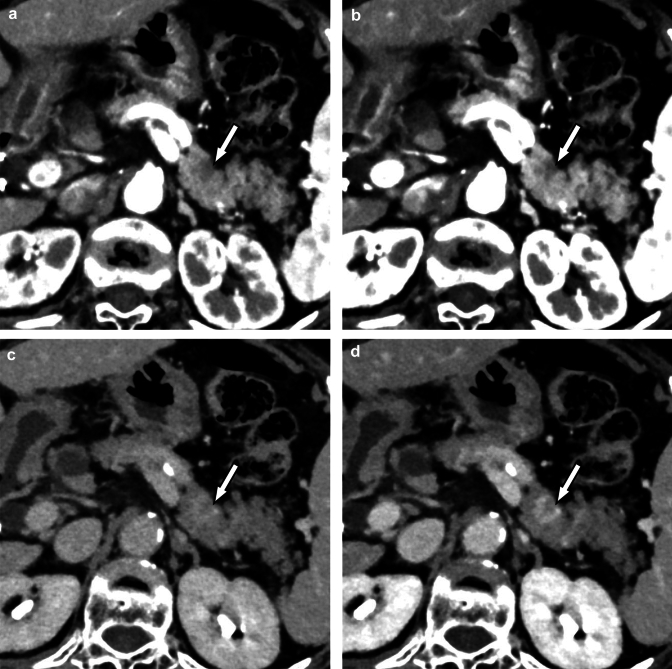

Fig. 11.

A small thrombus in the mesenteric vein (arrows) is visualized on the photon-counting CT images at 70 (A) and 50 keV (B). The 50 keV image (B) shows the thrombus with higher contrast than the 70 keV image (A). Photon-counting CT is excellent for visualization of venous thrombus

Thrombosis

Contrast-enhanced CT is also useful in the diagnosis of thrombosis. With photon-counting CT, even small thrombi can be clearly visualized, contributing to an accurate diagnosis [56] (Fig. 11).